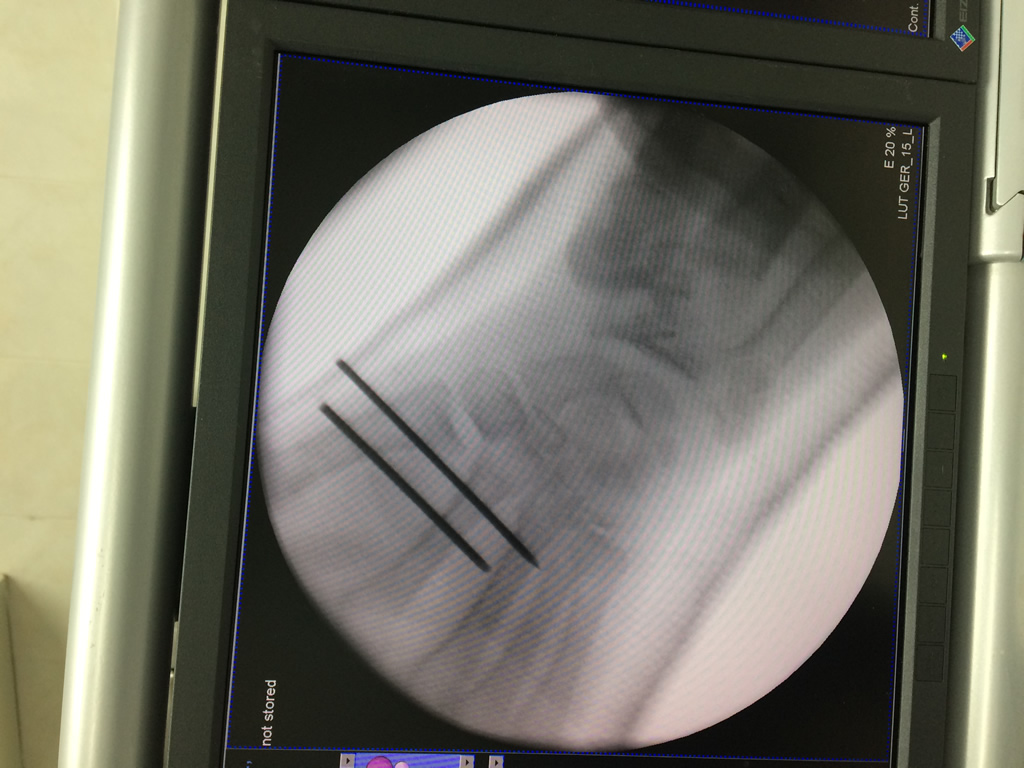

Cirugía de Muñeca y Mano

Los procedimientos más comunes en cirugía de la mano son aquellos destinados a reparar traumatismos, incluyendo lesiones de tendones, nervios, vasos sanguíneos, y articulaciones; huesos fracturados; y quemaduras, cortes, y otros daños de la piel.